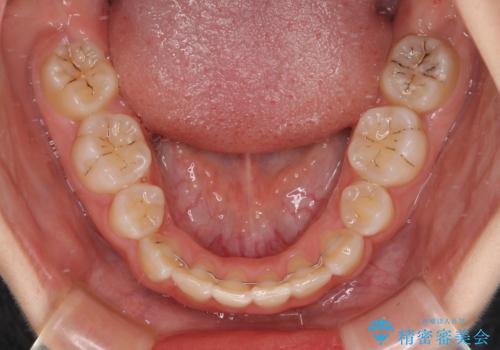

重度叢生と埋もれた奥歯 8本を抜歯したワイヤー矯正

- 内側に生えている歯や埋もれた奥歯を気にして来院された患者様です。

顎の骨が小さいため、歯列が収まりきらずに叢生や未萌出となっている状態でした。

埋もれた奥歯を萌出させ、さらにデコボコを解消するために、上下左右の第1小臼歯4本に加え、親知らず4本も抜歯し、ワイヤー装置にて矯正治療を行うこととしました。